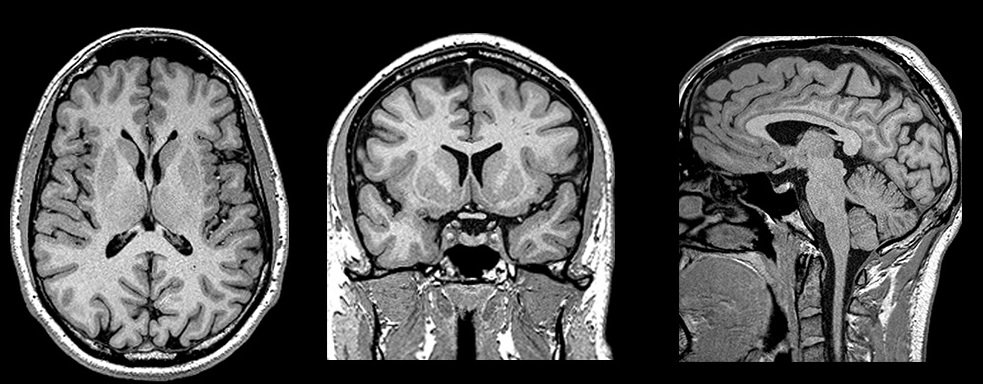

What has changed is the imaging. Neuroimaging studies now document white matter changes in fibromyalgia patients, particularly in regions involved in descending pain modulation, the pathways that normally regulate the intensity of pain signals before they reach conscious awareness. There is also evidence of small fibre neuropathy in a significant proportion of patients, actual structural changes to the thinly myelinated and unmyelinated peripheral fibres that carry pain and temperature signals.

The condition is not imagined. It is written in the white matter. The scanner was simply not looking in the right place.